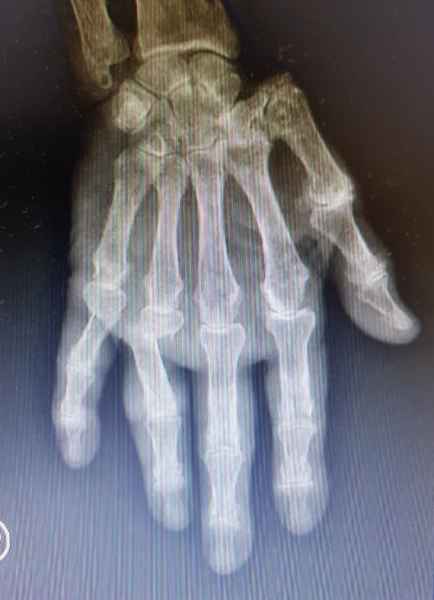

En la Artritis Reumatoidea el compromiso de las articulaciones interfalángicas proximales, metacarpofalángicas y de la muñeca estan generalemente afectadas simetricamente, lo que la distingue de la Artrosis, en la cual el compromiso se observa predominantemente en las articulaciones interfalángicas distales.

Cambios agudos como ser dolor o edema, pueden ser indicio de Artritis aguda o ataque de Gota aguda, los cambios crónicos tienden a modificar la estructura y anatomía normal de las manos como ser los dedos en cuello de cisne, mano en ventarrón, característicos de la Artritis, mientras que en la Gota crónica se observan tofos gotosos con deformidad de grandes articulaciones de la mano.